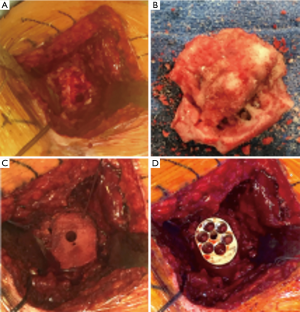

Gupta et al. (44) also presented a classification system to guide intra-operative decision-making for the management of glenoid bone defects (Figure 4). Defects are classified as centric (C), or eccentric (E), and then subclassified according to size (1 to 4) and location (anterior, posterior, inferior or superior). They reported 83% of eccentric (E), 63% of moderate to severe (grades 3 and 4), and 51% of anterior defects in a cohort of 54 revision RSAs (44).

Allografts may be chosen to avoid morbidity associated with harvesting iliac crest, obesity, or previous iliac crest bone harvest (44). Although several types of allograft have been described, the femoral neck has been the preference because its dimensions mimic the native glenoid size (42) (Figure 5).

Convex-back baseplates (Figure 6) recently introduced require less bone reaming and allow greater contact area between the baseplate and the native glenoid than flat-back baseplates (44). Convex-back baseplates has also demonstrated less tilt and displacement when subjected to eccentric loads when compared to flat-back ones, suggesting that convex designs may have better fixation and lower loosening rates (44). Anglin et al. confirmed this theory in a biomechanical study demonstrating that convex-backed baseplates lead to stress transmission in compression of the underlying bone rather than shear forces when compared with a standard flat-back design (56).